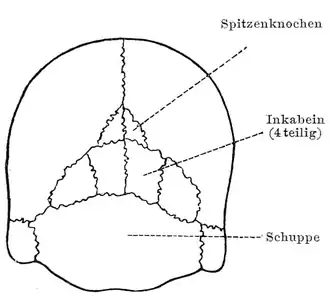

Multiple interparietal bones or Inca bones shown in a 20th-century anatomical illustration (with labels in German). | |

An interparietal bone (os interparietale or Inca bone or os inca var.[1]) is a dermal bone situated between the parietal and supraoccipital. It is homologous to the postparietal bones of other animals.

In humans, it corresponds to the upper portion of the squama of the occipital bone that lies superior to the highest nuchal line and is completely fused to the supraoccipital. However, in some individuals this portion remains separate from the rest of the occipital bone throughout life. In such cases, this separate bone is particularly referred as Inca bone. Inca bones in humans were first found in the skulls of contemporary indigenous peoples of the southern Andes as well as in those of mummies of the Inca civilization. Although the Inca bone was originally encountered as a variation in South American and Latin American cranial remains, the variation occurs in people from all geographic regions of the world and is by no means indicative of South/Latin American origin.